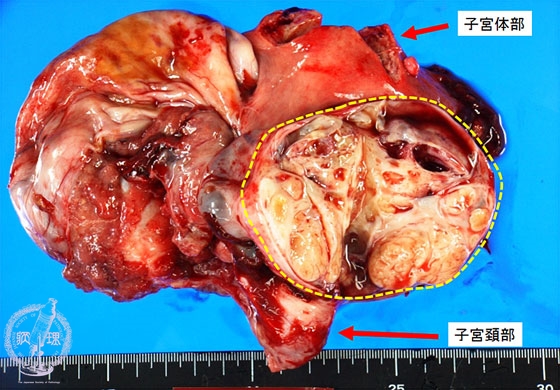

卵巣明細胞腺癌マクロ像(未固定新鮮標本)

マクロ像(未固定新鮮標本):卵巣嚢胞内には黄色調の充実性腫瘍(黄色点線)が認められる。